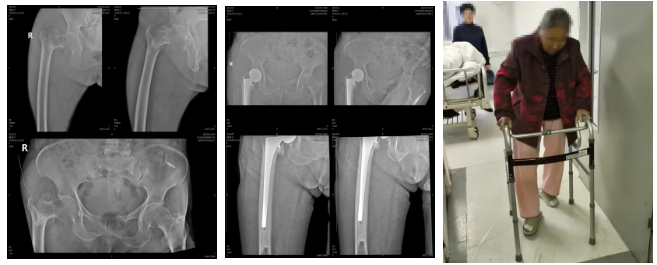

患者1:82岁的范爷爷既往患有冠心病 心功能II级、心律失常、腔隙性脑梗死。此次因摔伤致右侧股骨粗隆间骨折住院治疗。围术期和术中随时可能发生猝死、脑梗、心梗、脑出血、心力衰竭、呼吸衰竭等严重并发症,手术耐受性差。

术前: 术后: